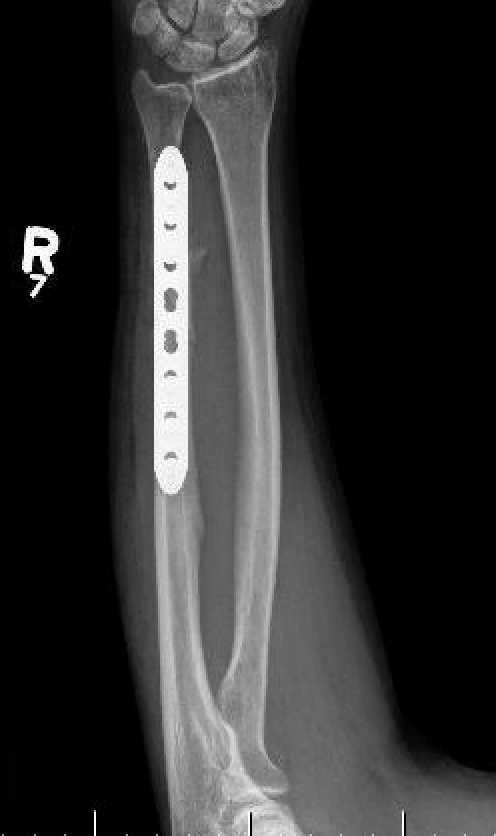

Compression plating

Results

- IM K wire v plate in 54 patients

- 3 nonunions with plate, none with IM wire

- 11% of patients required plate removal